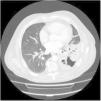

In the blood tests, the findings were as follows: leukocytosis with neutrophilia, raised C-reactive protein and procalcitonin, slight alteration of liver function tests, and B12 vitamin 991.70pg/mL. Chest radiography showed LLL opacity and urine antigens were negative for pneumococcus and legionella. All these findings were interpreted as LLL community-acquired pneumonia, and the patient received a 1-week course of levofloxacin 500mg. There was no clinical or radiological improvement, so the drug therapy was adjusted to moxifloxacin 400mg for 21 days. One month later, the patient attended our clinic. No changes were detected in the radiological image, so additional studies were implemented. A chest CT was performed (Fig. 1), showing a LLL opacity with air bronchogram, and multiple images of cavities with necrosis and bronchiectasis. The flexible bronchoscopy showed no endobronchial, bacterial or anatomopathological findings. Finally, we performed a CT-guided biopsy on the LLL lesion. Pathology results reported a low-grade B-small cell non-Hodgkin lymphoma, compatible with marginal MALT-type lymphoma associated with vascular and stromal lambda amyloidosis type A. This case was reviewed by the haematology department, who requested an abdominal scan, a positron emission tomography (PET) and an echocardiogram. Finally, the patient received radiotherapy to the lesion.